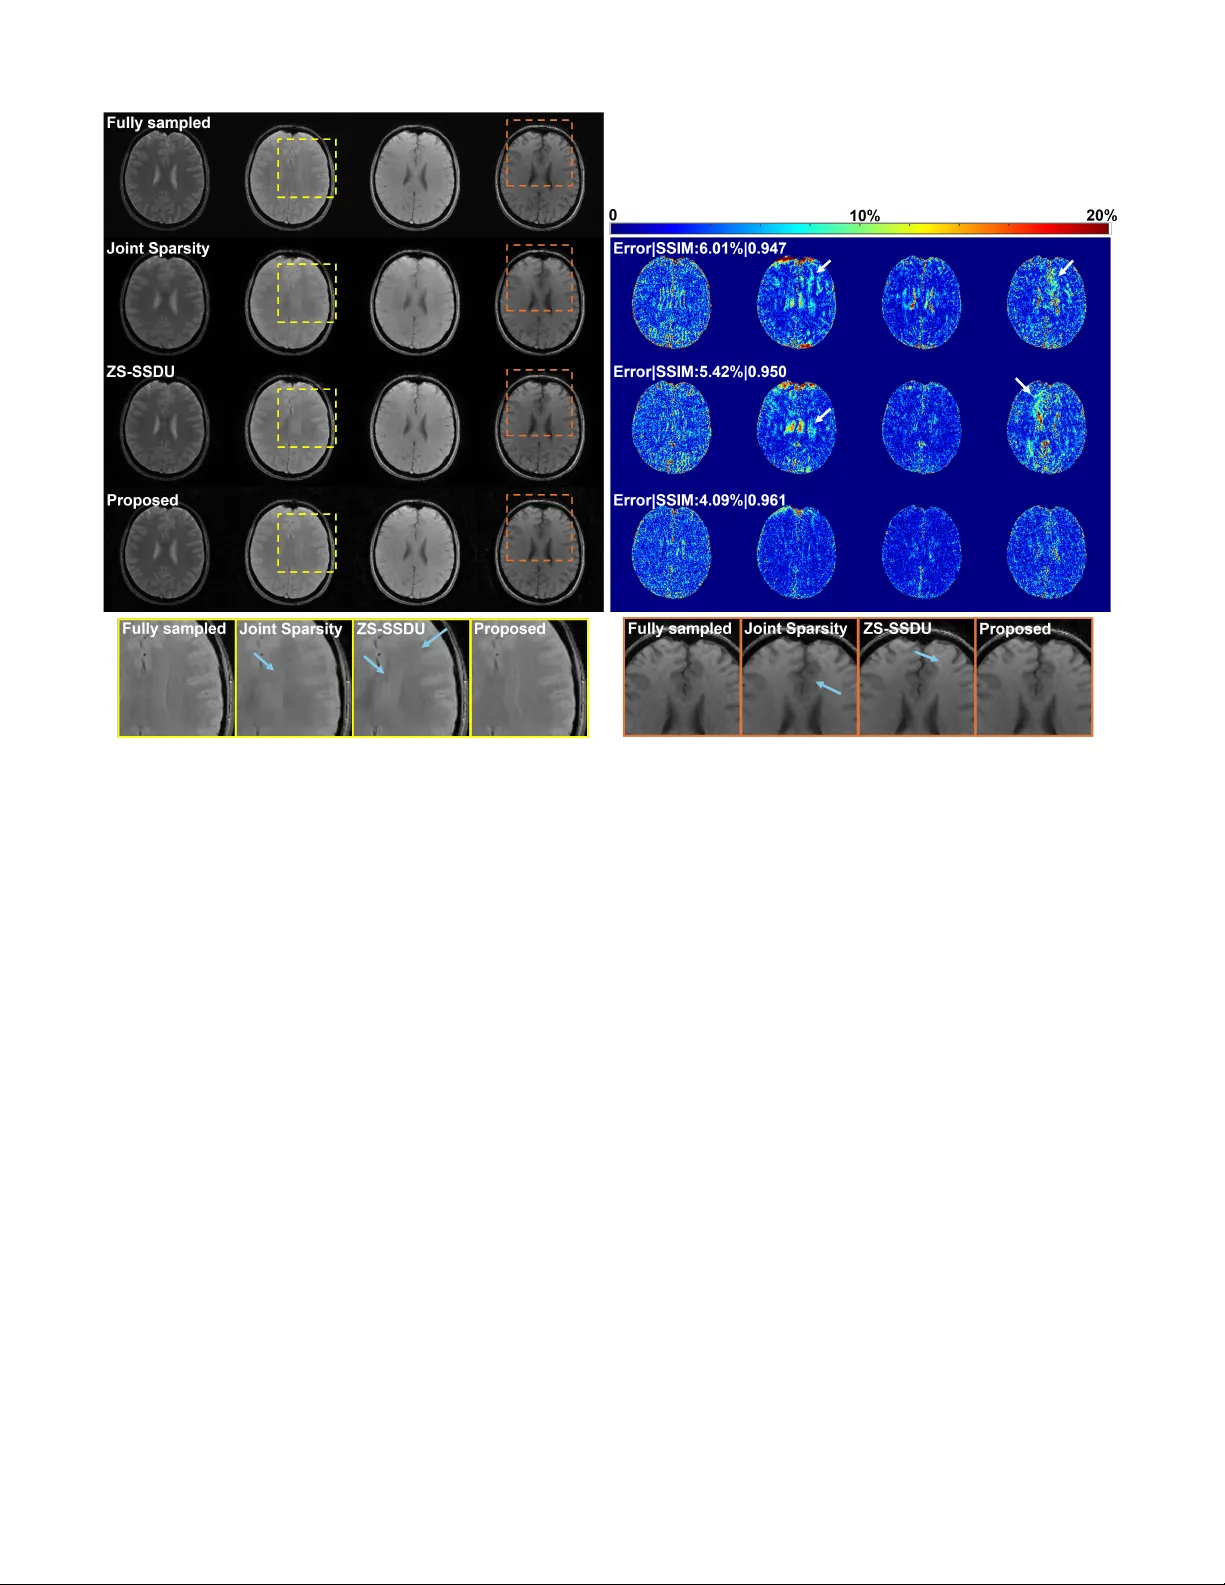

실험 결과는 가속된 T1·T2 매핑(예: 4×, 6× 가속)에서 기존 최첨단 방법들(예: LORAKS, MoDL, DDPM 기반 재구성)보다 PSNR·SSIM·NMSE 모두에서 평균 1.5~2.0 dB 향상을 보였으며, 특히 저신호 영역에서 잡음 억제가 두드러졌다. 중요한 점은 태스크‑특정 지도학습이 전혀 필요 없었다는 것이다. 즉, 사전 학습된 분리 표현과 제로샷 적응만으로 다양한 파라미터 매핑에 일반화가 가능함을 입증했다.